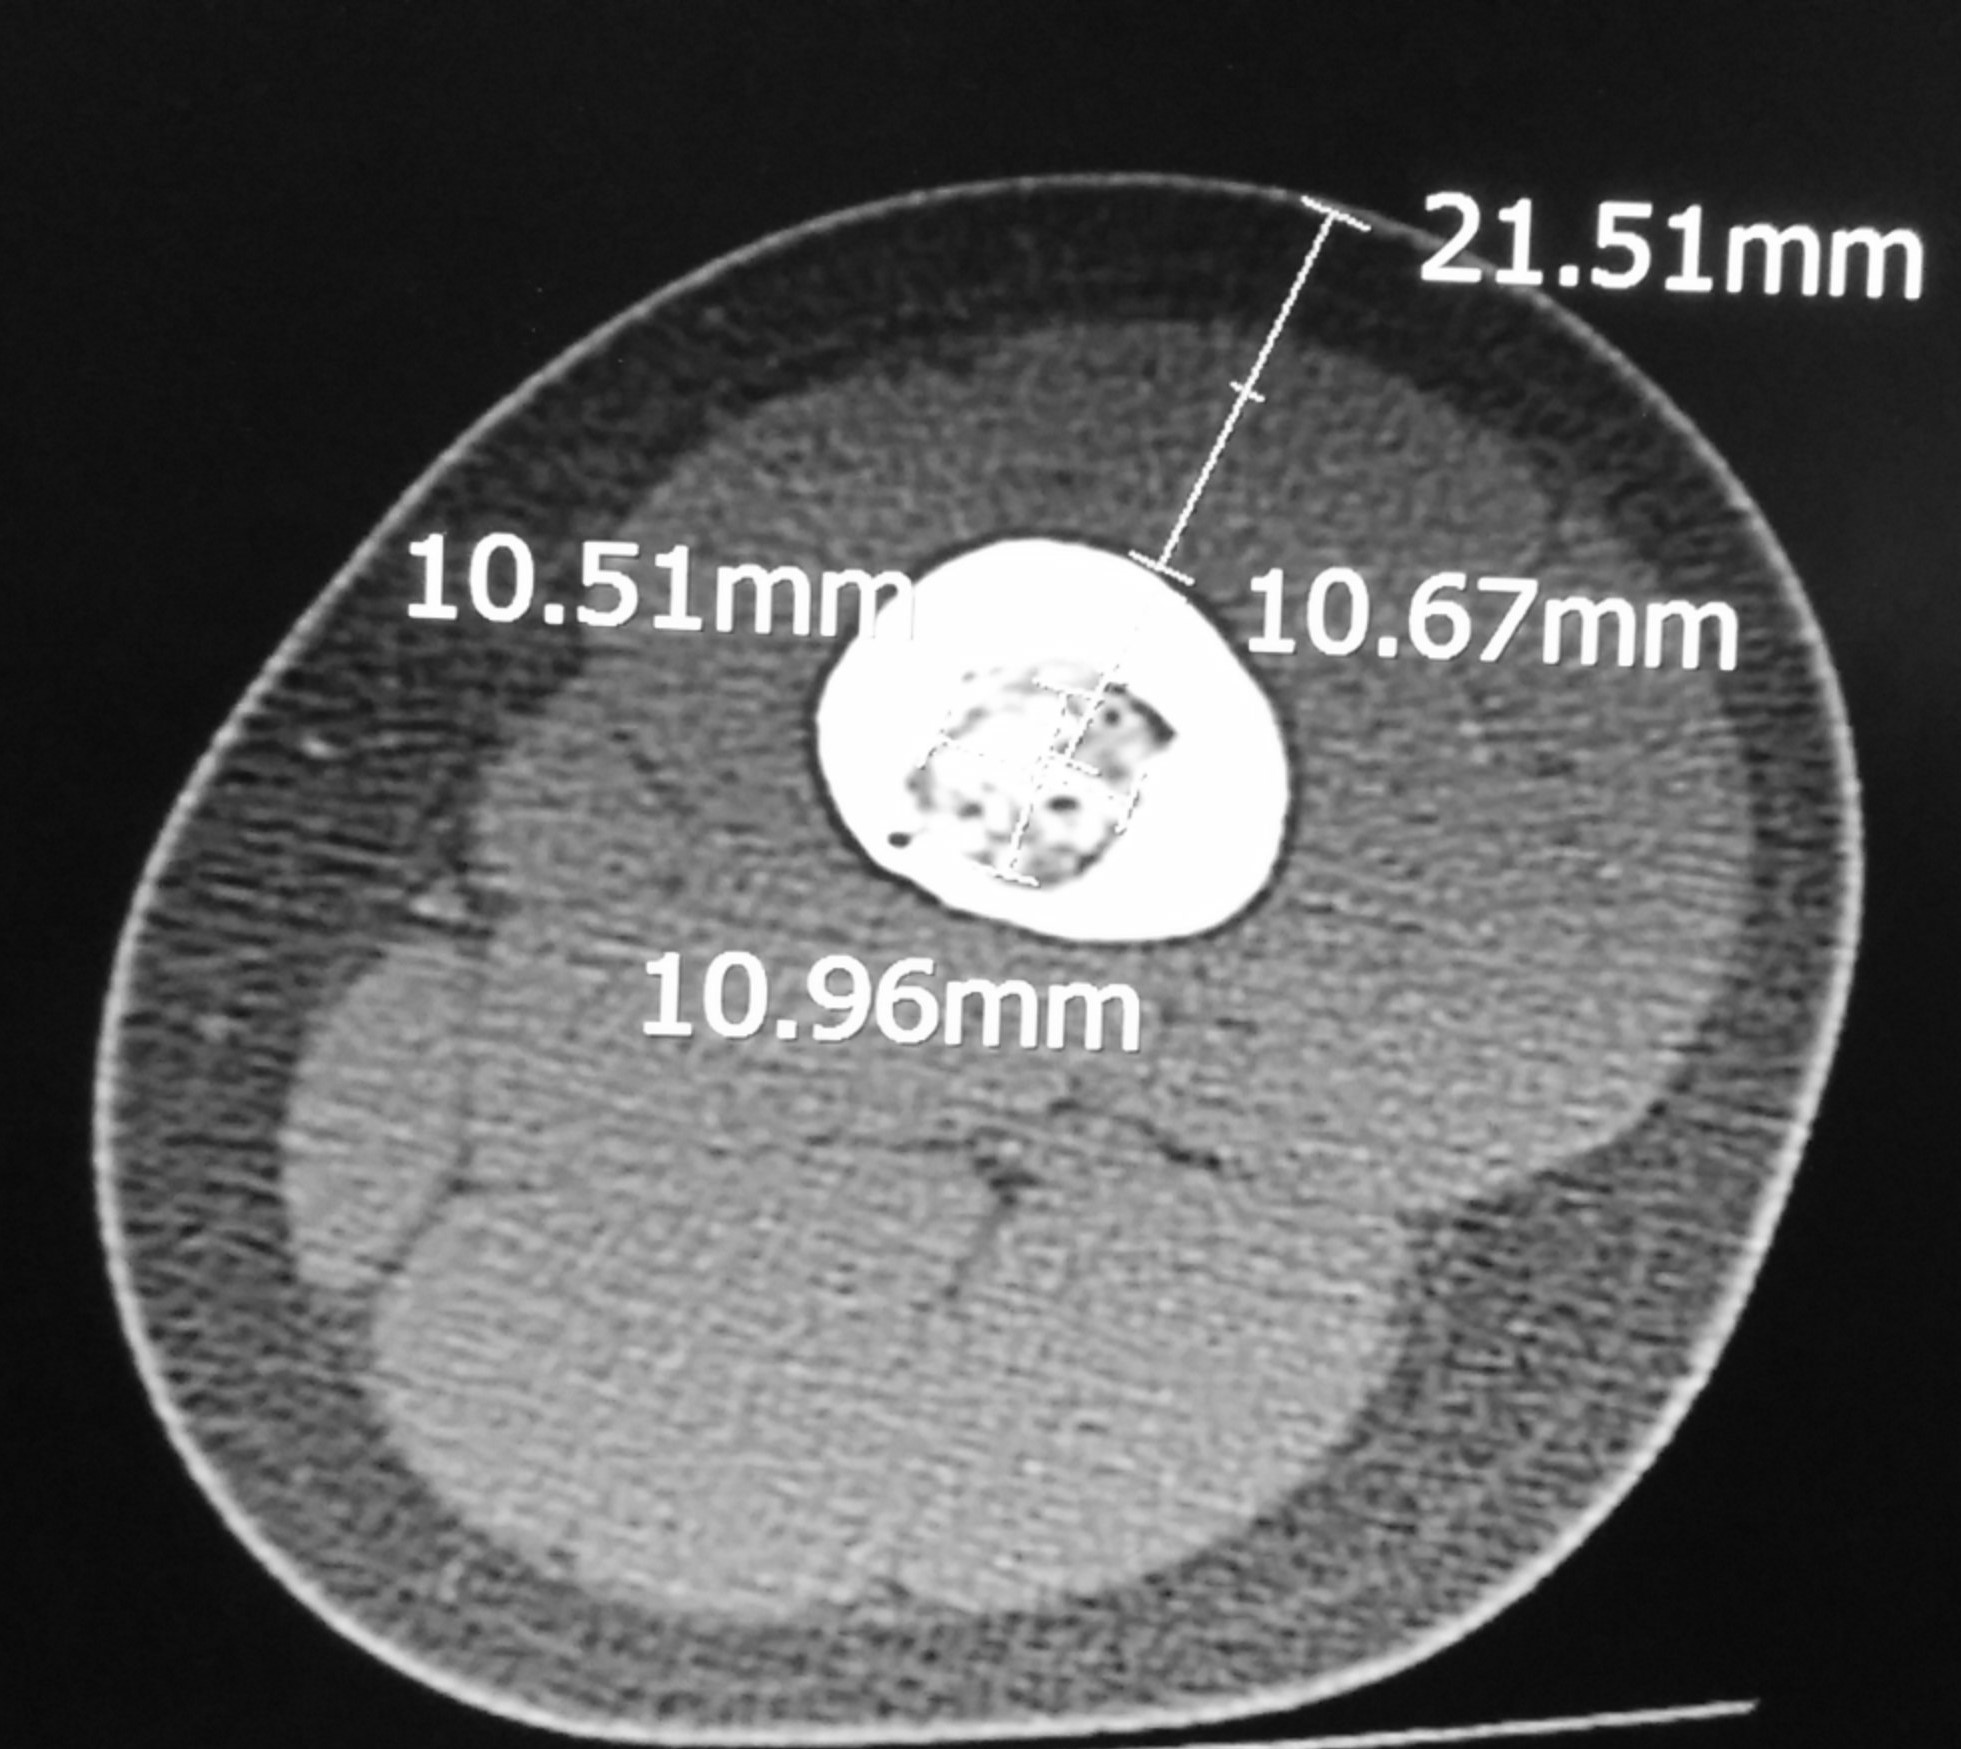

X-rays of the left femur showed the characteristic nidus surrounded by a zone of reactive bone.

CT-scan was done to further evaluate the lesion. It confirmed the diagnosis based on the typical features.

The CT-scan also showed muscle atrophy of the left thigh muscles compared to the right thigh.